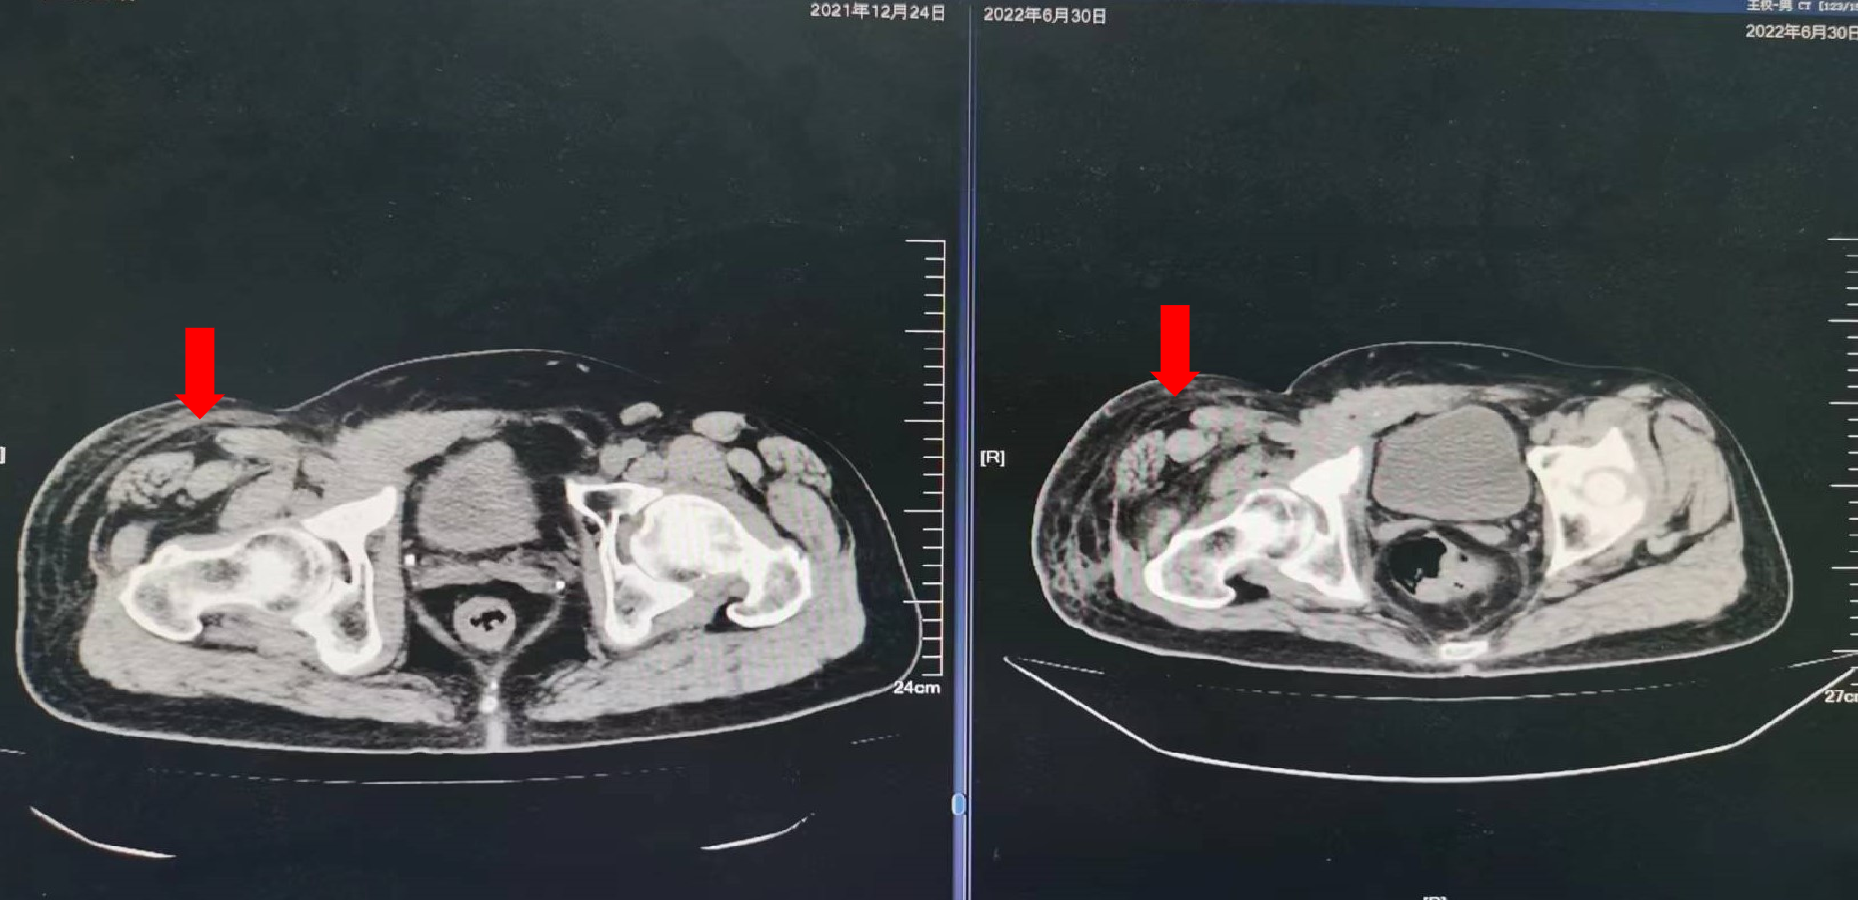

2021年5月27日:开始口服曲氟尿苷替匹嘧啶片(TAS-102)55mg每日2次 d1-5,d8-12,Q4W配合信迪利单抗免疫治疗。

疗效评价:SD,患者右腹股沟肿胀疼痛明显减轻,停用止痛药,PFS时间为10个月,主要不良反应为Ⅱ度骨髓抑制。